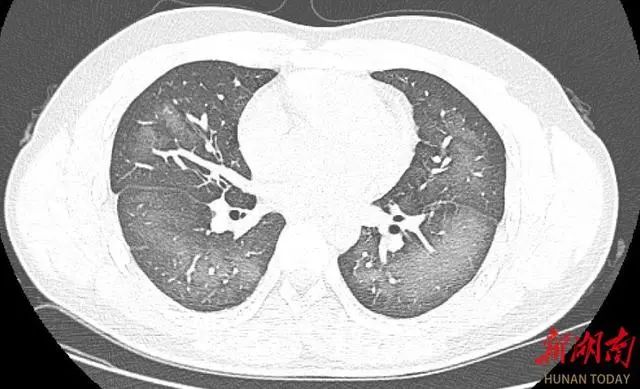

经检查,肺部CT片显示,李林双肺赫然呈现大范围白色样病变,报告提示“白肺”。

“白肺”一般是指重症肺炎在X线或CT检查下的表现,患者肺部呈现一大片的白色状态,往往会出现呼吸困难、呼吸衰竭,严重者还会出现其他脏器功能障碍。